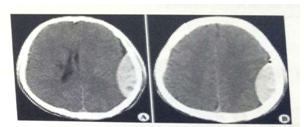

試題2:男,44歲。頭部外傷12小時(shí)。結(jié)合CT片,此診斷為(2分)

A.硬膜下血腫

B.腦出血

C.硬膜外血腫

D.顱骨骨折

E.腦血栓

答案:C

影像學(xué)2